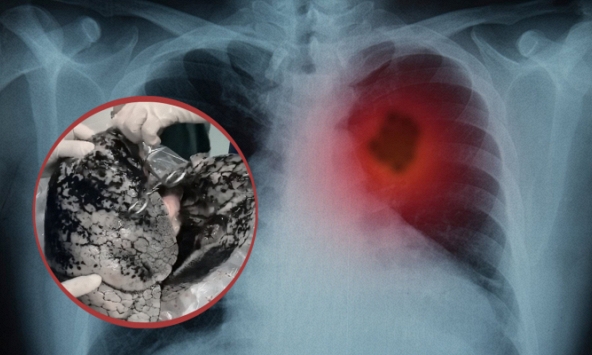

| Ảnh minh họa |